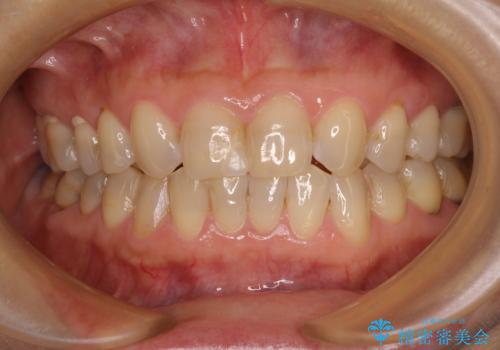

- 上顎2前歯の色を気にして来院された患者様です。

2本ともに虫歯治療による充填材の変色などによりつぎはぎのような前歯となっていたため、オールセラミッククラウンにて補綴治療を行うこととしました。

今後ホワイトニングをする予定とのことで、少し明るめのトーンに仕上げました。